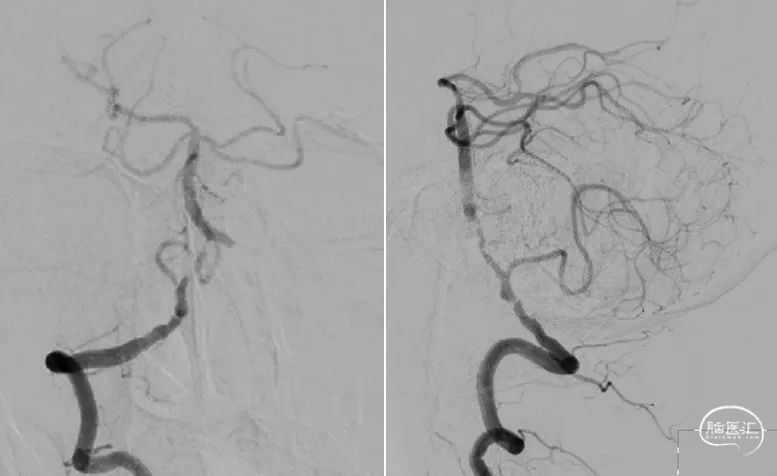

左椎动脉+左颈动脉造影:

右椎动脉造影:

右颈动脉造影:

右椎动脉动脉正侧位:

1.右侧椎动脉V4段重度狭窄(90%);

2.高血压病2级 高危;

3.小脑梗死。

病变情况分析:右桡动脉穿刺,置6F桡动脉鞘管,5F多功能导管在泥鳅导丝辅助下脑血管造影提示:右椎动脉V4段重度狭窄(约90%)。